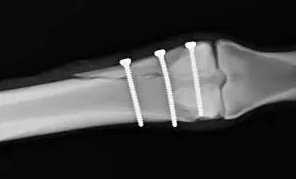

経皮的ピンニング

骨折の整復後に経皮的ピンニングを行う方法は、依然として一般的な手術固定法です。キルシュナーワイヤー(Kワイヤー)固定は、低侵襲性の選択肢であり、外科医が安定化パターンを柔軟に選択でき、軟部組織への損傷を最小限に抑えることができます。しかし、Kワイヤーは、スクリュー、プレート、釘を用いたより安定した固定法と比較して、固定が失われるリスクが高くなります。

文献1】より